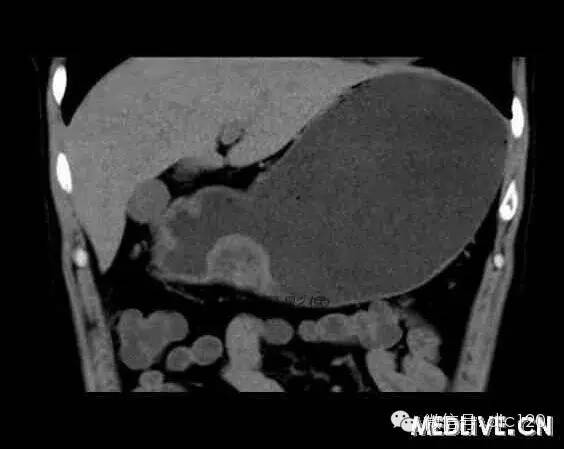

男,36歲,間斷性返酸噯氣3年,3個月前出現上腹疼痛,饑餓時加重。圖1-3為CT平掃,圖4-6分別為CT增強掃描的動脈期、門脈期和延遲期。

CT檢查可見胃幽門前區胃小彎側胃壁局限性增厚、隆起或伴凸向胃腔內的小結節灶,寬基地,境界光整,注射對比劑,增強掃描后,CT值可達50HU以上,與正常胰腺強化相仿。

胃迷走胰腺大多位在距幽門1-6cm的胃竇胃大彎側,粘膜下層內,為1-3cm大小的病灶。 與胃壁以寬基底相,增強掃描病灶表面覆蓋的黏膜明顯強化且連續,病灶內無明顯壞死,病變強化方式類似于正常胰腺組織;當病灶出現邊緣臍凹征或中央導管征時,對EP的診斷具有一定的特異性。